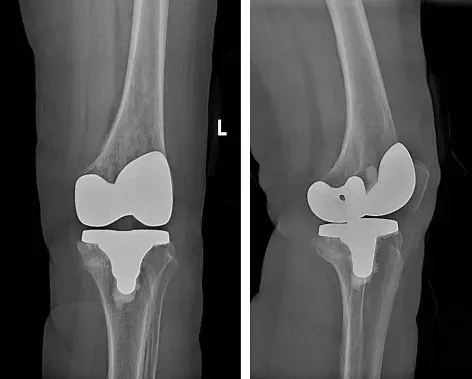

术前准备完善后,北京大学第三医院关节外科专家赵旻暐主任医师来到我院,通过术中定位、截骨、试模、安装膝关节假体等一系列复杂操作,为两位患者先后实施了单侧人工全膝关节表面置换术。由于手术切口较小,疼痛较轻,术后第一天,他们便在医生指导下,手扶助行器迈出了意义非凡的“第一步”。看到患者术后恢复的这么好,家属脸上露出了满意的笑容,对北京专家的诊疗技术称赞不已。

人工膝关节置换术作为膝关节骨性关节炎治疗的手术方法,随着对膝关节生物力学研究的不断深入,膝关节假体设计理念不断更新,人工膝关节置换手术也日趋成熟,通过采用高分子聚乙烯和金属等假体置换受损的关节,可重建膝关节解剖结构,恢复生理解剖构造,对于恢复患者正常行走能力,改善膝关节功能,提升生活质量,有着重要的意义。